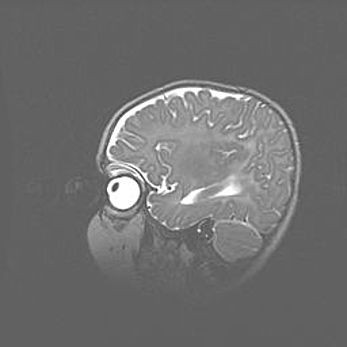

Аномалия Денди-Уокера. Признаки гипоплазии мозолистого тела.

Возраст: 5 месяцев 3 дня

Вес: 5550 г

Пол: мужской

Окружность головы: 39 см

Срок гестации: 40 недель

Аномалия Денди-Уокера – это порок развития головного мозга, для которого характерна триада симптомов: гипотрофия или аплазия червя мозжечка и/или полушарий мозжечка, расширение четвёртого желудочка с формированием ликворной кисты задней черепной ямки, гипертензионная гидроцефалия различной степени.

Гипоплазия мозолистого тела относится к дефектам внутриутробного этапа развития мозговой ткани, возникающим в процессе закладки структур головного мозга, что происходит на начальных этапах развития эмбриона.